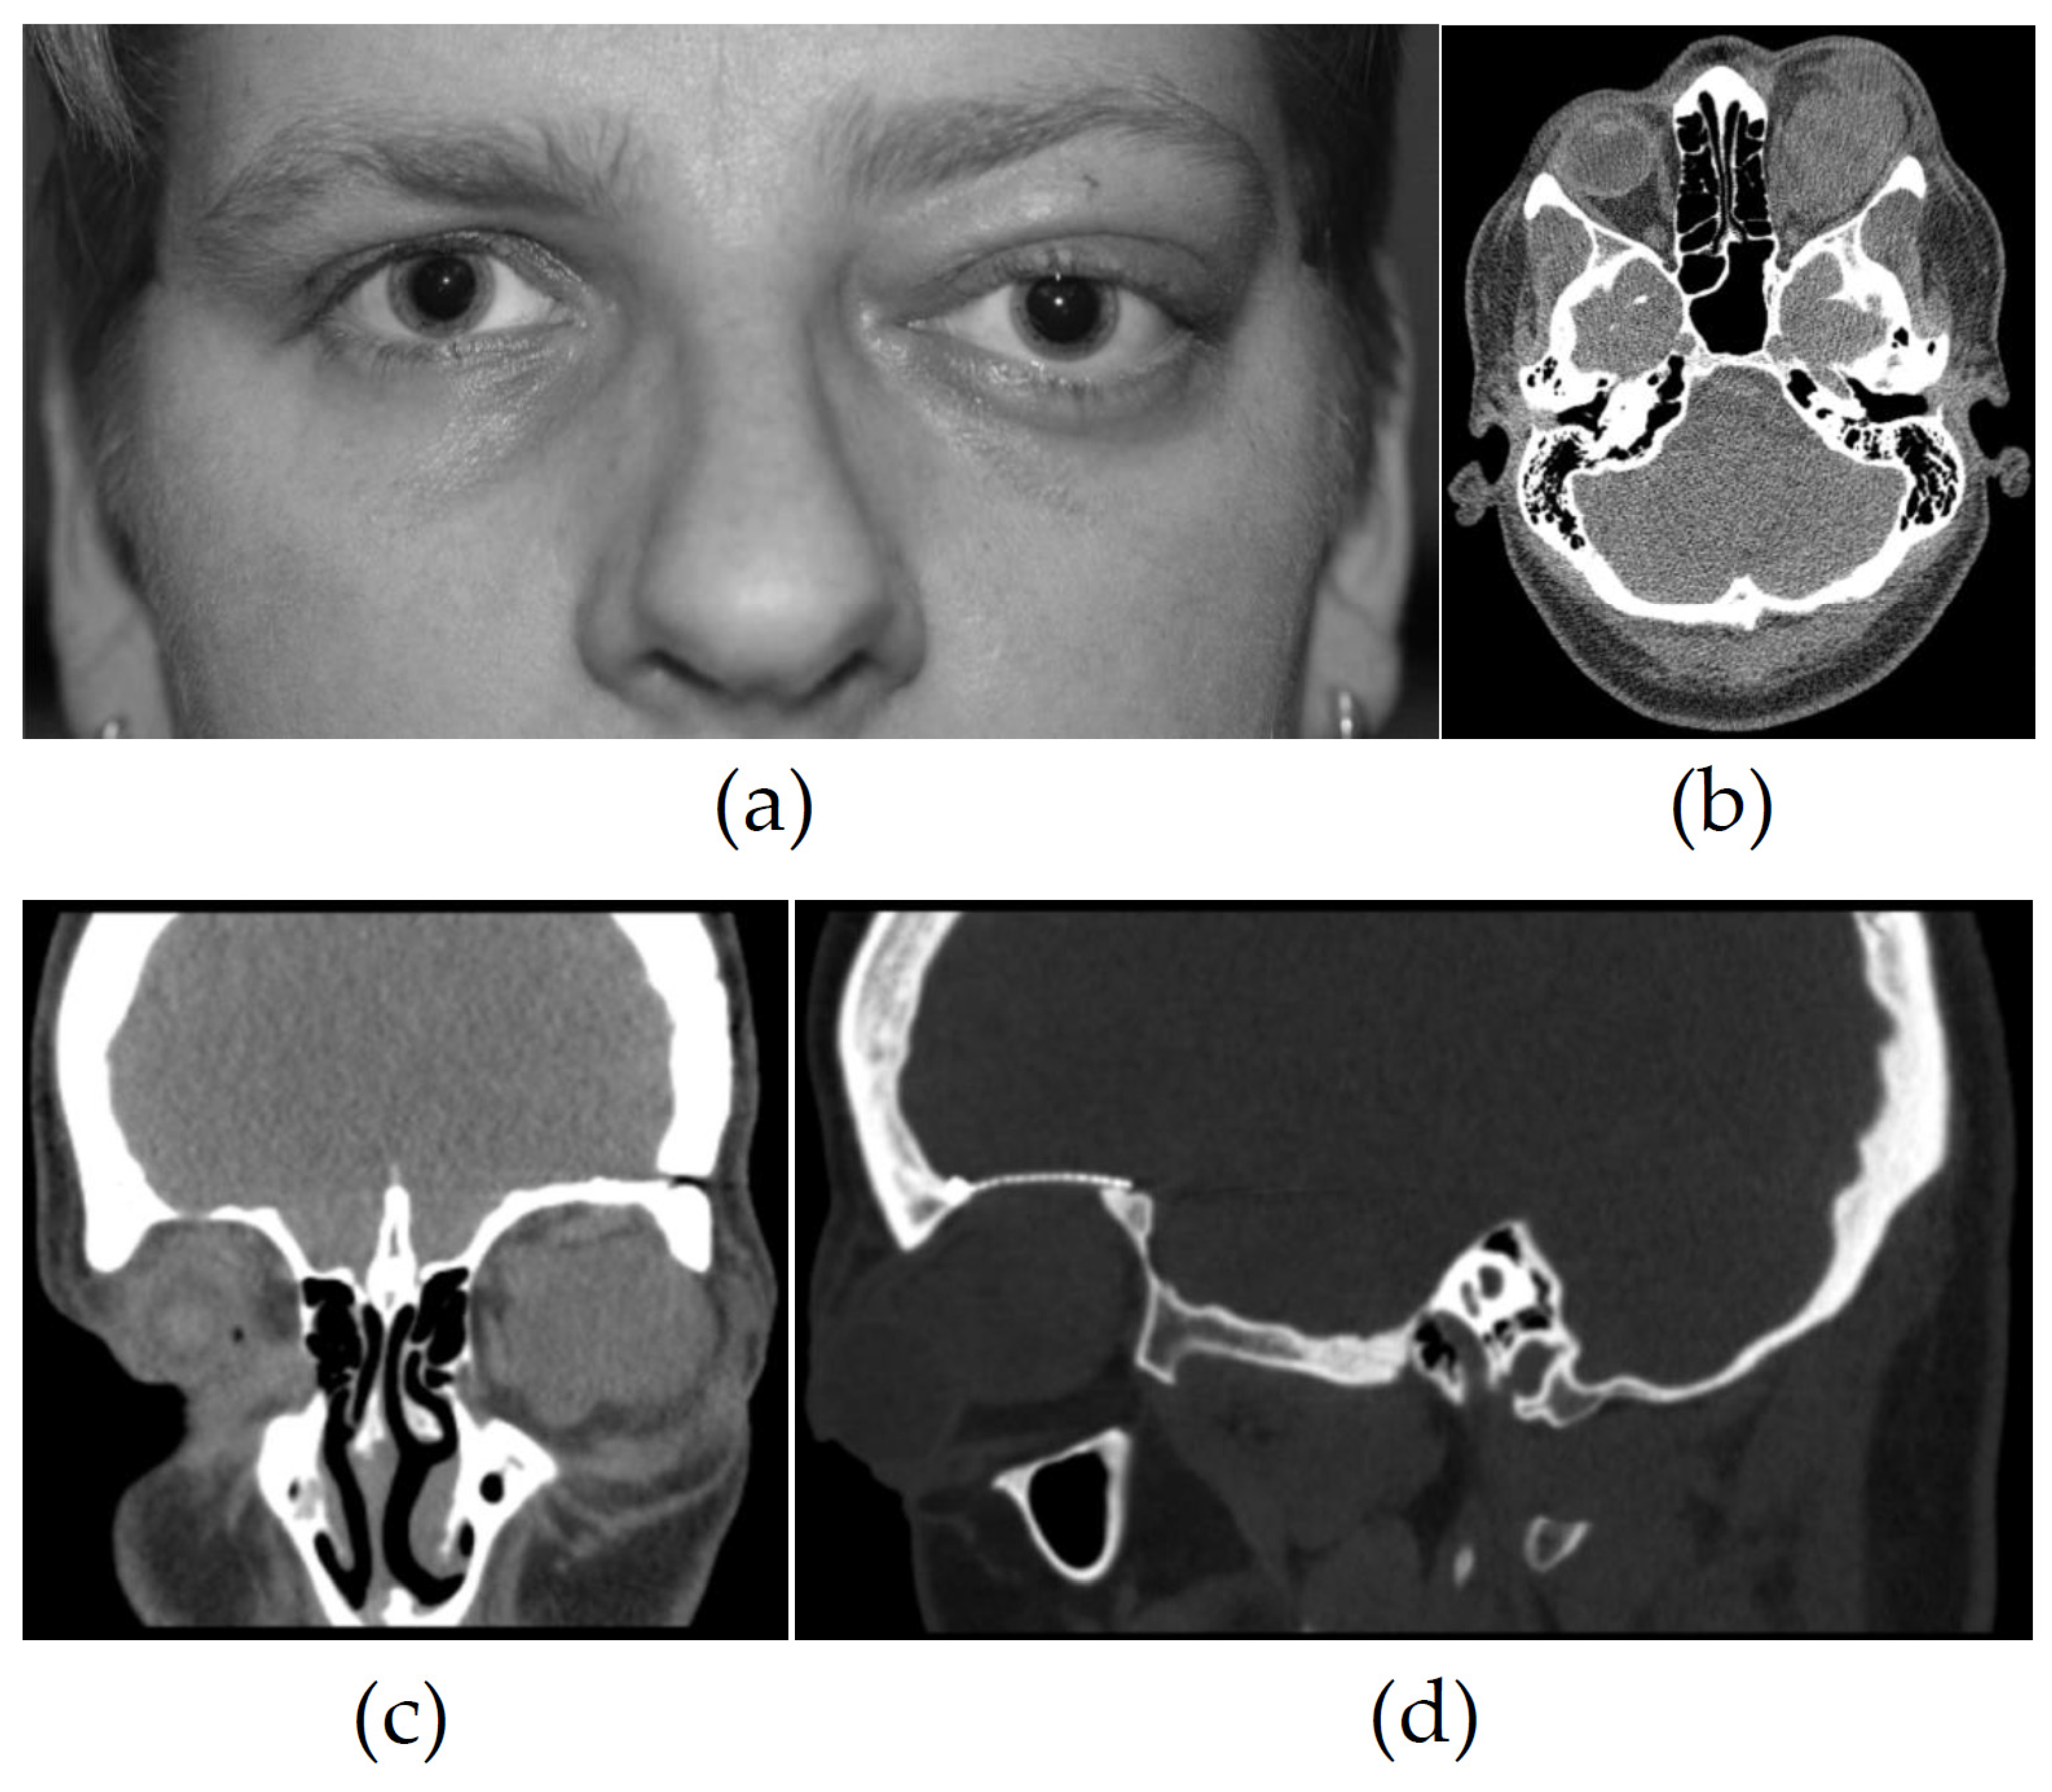

3.2. Imaging

| 7 | Hyperdense | Hypointense | Intermediate | − | Reduction | Inhomogeneous | Few vessels, inhomogeneous intratumoral lesions, compression signs, suspicion of osseous infiltration |